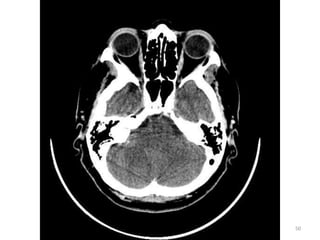

1. Medula espinal

(forame magnum)

2. Células mastóideas.

3. Seio maxilar esq.

4. Côndilo

mandibular(cabeça).

5. Processos zigomáticos.

6. Maxilar.

7. Osso nasal.

31

1. Cristalino do olho D.

2. Lobo parietal E.

3. Medula Oblonga

(bulbo).

4. Seio esfenoidal.

5. Corpo vítrio (globo

ocular).

6. Hemisfério cerebelar D

34

1. Músculo reto medial D.

2. Músculo reto lateral E.